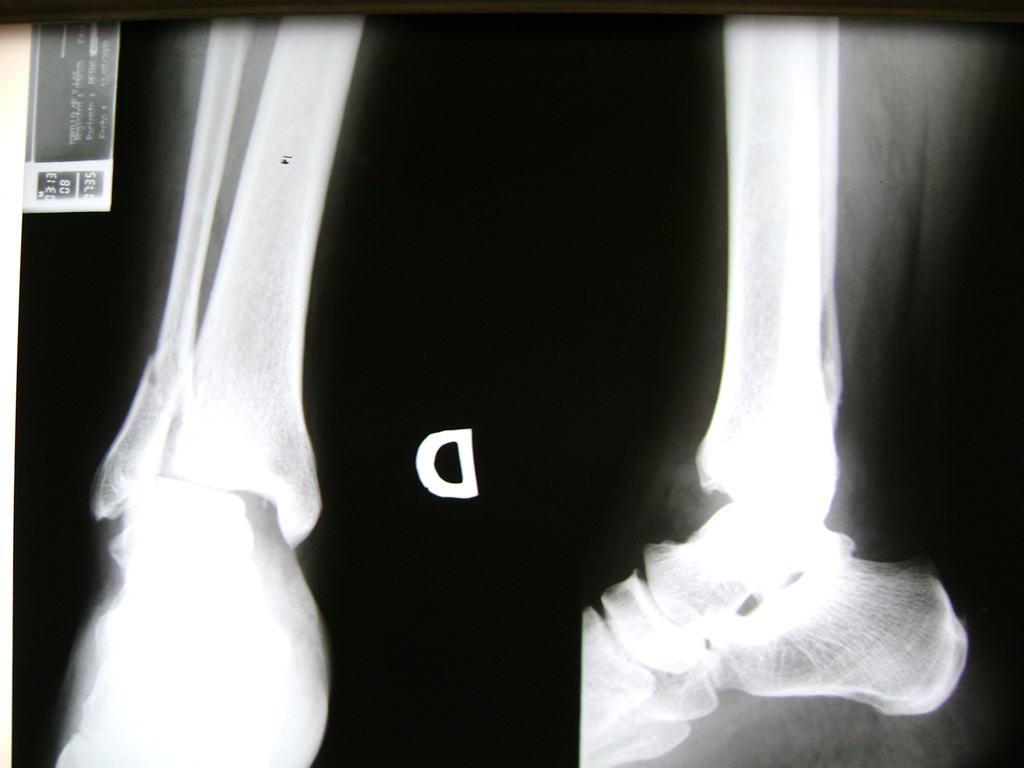

Una fractura de tobillo es la rotura de uno o más de los huesos del tobillo. Estas fracturas pueden ser:

Algunas fracturas de tobillo pueden requerir cirugía si:

- Los extremos de los huesos están desalineados entre sí (desplazados).

- La fractura se extiende hasta la articulación del tobillo (fractura intra-articular).